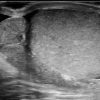

Viêm tinh hoàn - mào tinh

Viêm tinh hoàn – mào tinh

» Thông tin: Nam giới – 34 tuổi.

» Lâm sàng: Sưng đau vùng bìu.

# Tăng kích thước và tín hiệu mạch trên doppler tinh hoàn và mào tinh hoàn.